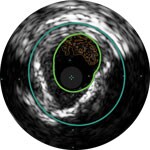

Behandlungsplan Beispiel 1

Lumen

Exzentrische fibröse Plaque mit tiefliegendem Calcium

Schallschatten

Gefässgrösse: 5,5 mm Durchmesser Plaquemorphologie: fibröse Plaque mit intimalem und mittlerem Calcium Plaquegeometrie: exzentrische Läsion Position des Führungsdrahtes: wahres Lumen

Quick-Cross-Katheter: souverän komplexe Morphologien durchqueren Direktionale Atherektomie mit Phoenix: frontal zum Schneiden, Erfassen und Freilegen gemischter Morphologien, einschliesslich Kalzium; Möglichkeit der Richtungssteuerung für grösseren Lumengewinn AngioSculpt Scoring-Ballonkatheter: Calcium messen, um eine Dissektion zu reduzieren4 Stellarex DCB: entwickelt für hohe Leistungsfähigkeit bei Kalzifizierungen